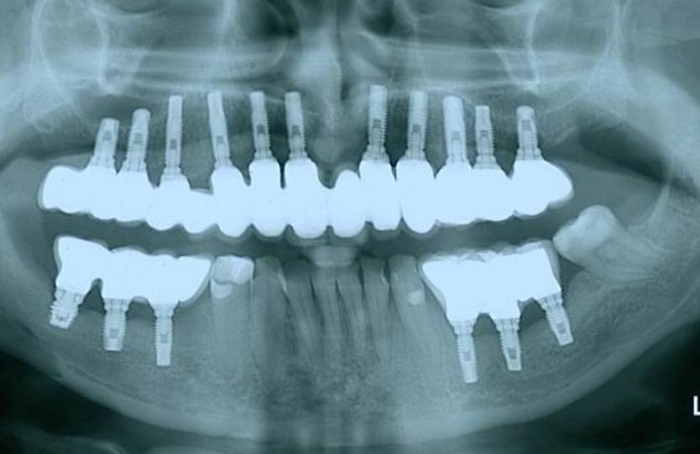

Raio X final

Raio X de controle, 24 meses após instalação das próteses fixas sobre implantes